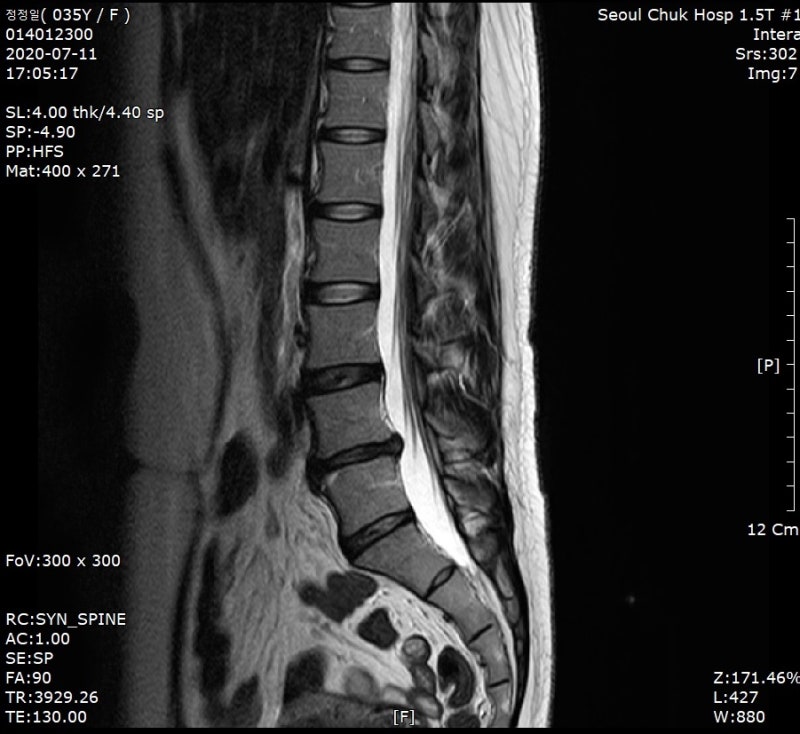

디스크 검사 및 치료 디스크 질환은 MRI와 엑스레이를 중심으로 검사를 실시합니다. 디스크가 발생한 경우에는 당연히 디스크를 치료해야 하지만 이를 검사할 때 척추의 구조나 상태를 종합적으로 진료해야 합니다. 요추의 인대나 힘줄은 어떤지, 척추의 구조는 어떤지, 또 디스크의 파열 정도나 상태를 파악해서 치료를 진행하는 것이 중요합니다. 디스크 치료는 보존 치료를 통해서도 호전을 기대할 수 있을 정도로 예후가 좋은 편이지만, 만약 특별한 상황이라면 수술적 치료를 고려할 수도 있습니다. 디스크 질환은 사람마다 다를 수 있으므로 정확한 검사와 진단으로 치료를 진행하는 것이 좋습니다.